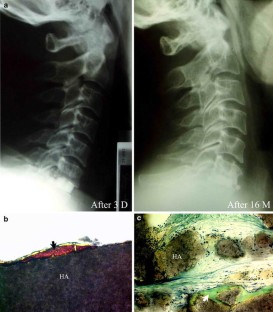

Few histological studies on bone substitutes in human cervical spine are available and the biological processes of bone substitutes are not well documented. The authors studied four failure cases of cervical interbody fusion: two cases with hydroxyapatite (HA), one case with β-tricalcium phosphate ceramic (β-TCP) and one case with xenograft (bovine bone). Clinical data showed that all the patients experienced neck pain with or without numbness of upper extremity due to fusion failure. Successful fusions were achieved after the salvage surgeries in which autograft were used. Radiographs showed that radiolucent lines were present in all cases. Two HA substitutes fractured without complications. One of them sank into the vertebral body. Some small β-TCP fragments were found under the microscope. Histological study demonstrated only a few newly formed bones at the interface of the substitutes. The fragments of HA were encapsulated by fibrous tissue. The degradation process and bone regeneration were more active in β-TCP than in HA. The intertrabecular spaces of bovine bone were filled with fibrous tissue. The results suggest that a porous calcium phosphate ceramic with special design might assure bone ingrowth and meet the mechanical requirements in cervical interbody fusion. The complications of these materials in the cervical spine should be highlighted.

Fig. 2